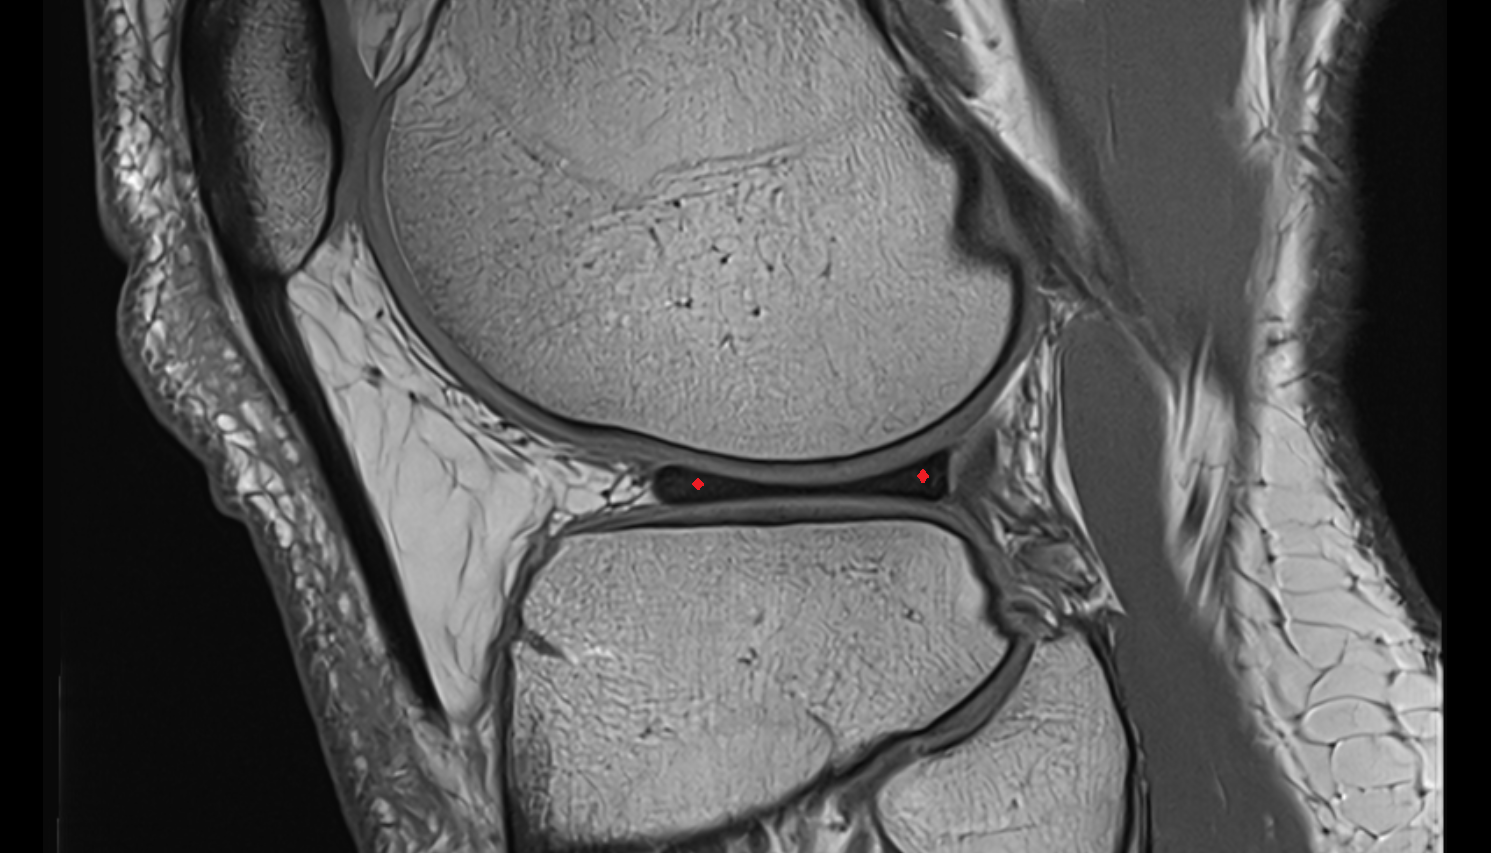

- Medial meniscus

- Lateral meniscus

- Anterior horn of medial meniscus

- Posterior horn of medial meniscus

- Body of medial meniscus

- Anterior root of medial meniscus

- Posterior root of medial meniscus

- Anterior horn of lateral meniscus

- Posterior horn of lateral meniscus

- Body of lateral meniscus

- Anterior root of lateral meniscus

- Posterior root of lateral meniscus

- Knee Joint